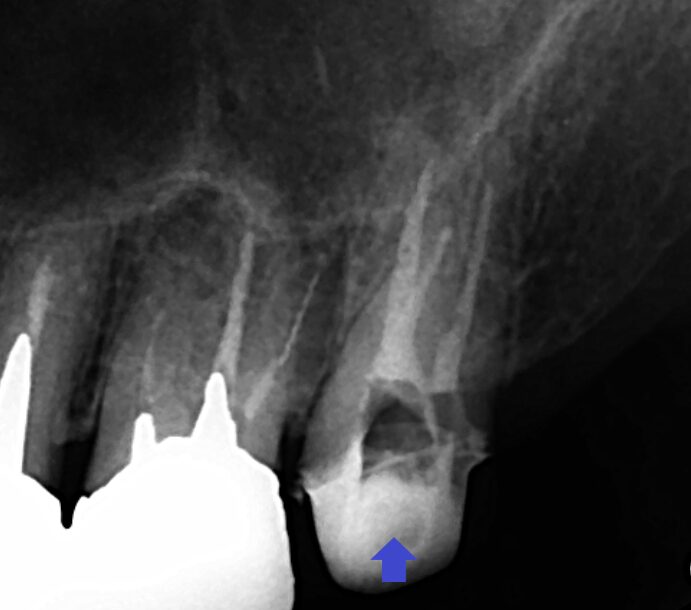

根管治療不足が原因で膿んでいることが考えられたため、精密再根管治療を行いました。画像は、根管充填時のレントゲン画像です。